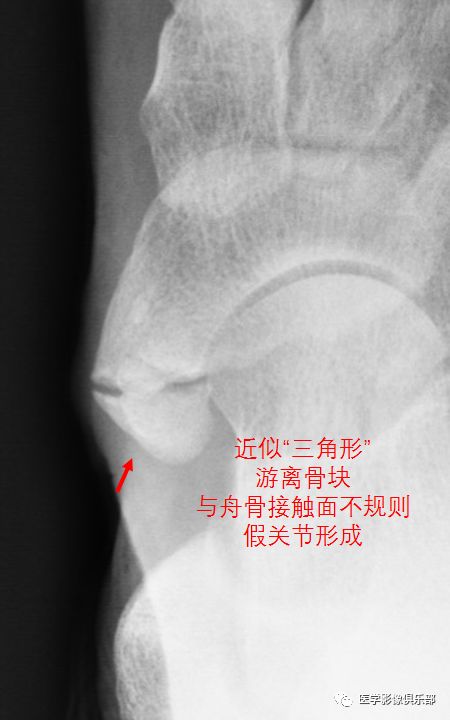

足副舟骨痛综合征

2型副舟骨和舟骨结节间以纤维软骨相连,受到外伤后关节损伤,出现炎症。